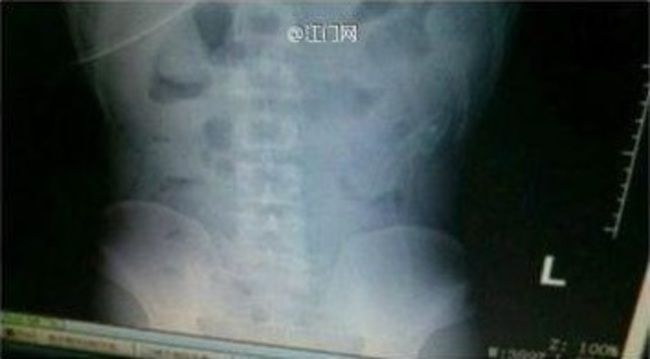

肛門にウナギを入れた男のレントゲン写真が流出

gif_animation 中国での珍事件。おそらくは ”性的な欲求” のために自分の肛門にウナギを入れた男。女医がネット上に公開したというレントゲン写真。[4]images